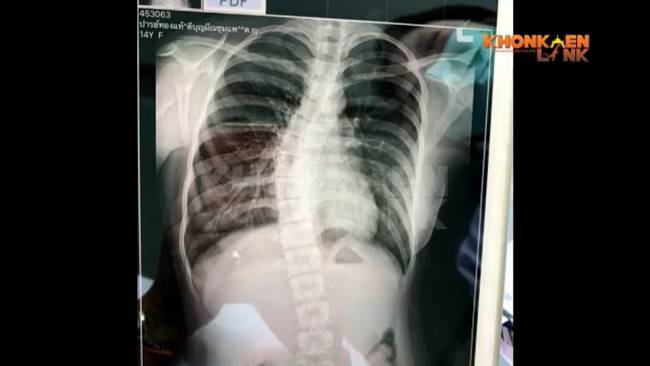

นางสุภาพ เปิดเผยว่า ตนรู้ว่าลูกกระดูกสันหลังคดงอหลังจากลูกสาวป่วยเป็นไข้ และไอ จึงได้พาไปหาหมอ และมีการเอกซเรย์ปอด แต่ผลปอดปกติ ลูกสาวเป็นแค่ไข้ธรรมดาและหลอดลมอักเสบ ซึ่งภาพเอกซเรย์ปรากฏให้เห็นว่ากระดูกสันหลังคดงออย่างมาก โดยที่หมอสันนิษฐานว่าเกิดจากการแบกของหนัก